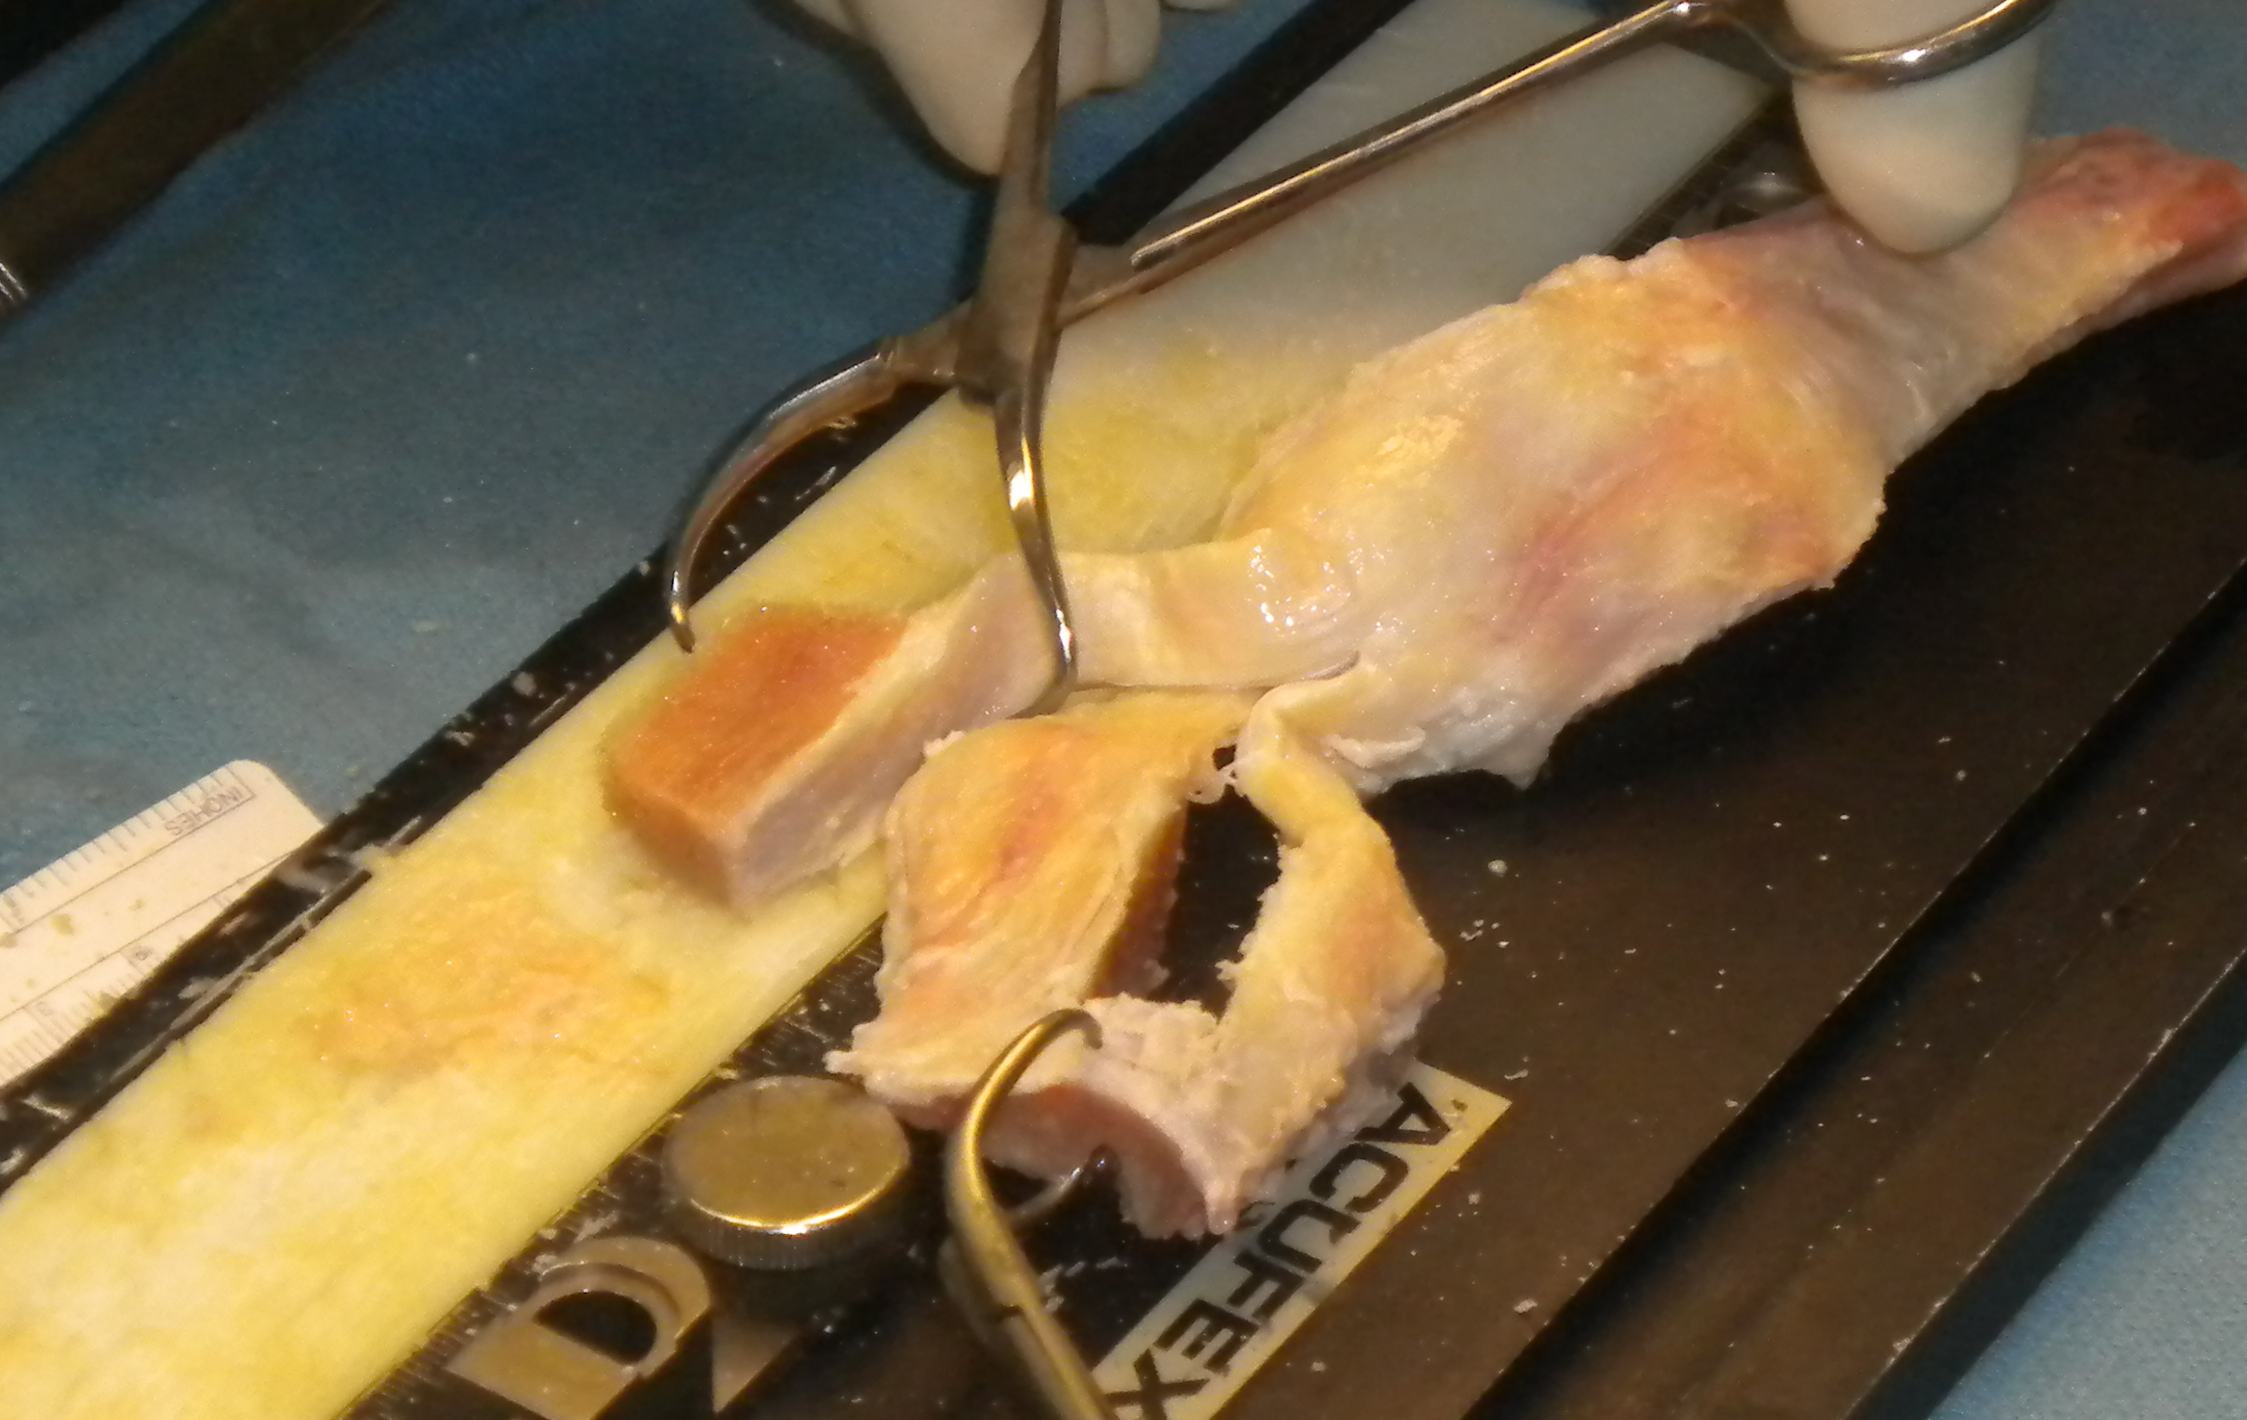

Length of bone femoral side

- usually 20 mm on femoral side

- this is usually from the patella

- cut with saw on each side

- turn and cut so is 10 mm thick

Length of bone on tibial side

- depends on fixation method

- risk is donor-recipient mismatch

- best to keep this side long / take from tibial end of graft

Graft mismatch

- if donor tendon too long for recipient knee, all bony graft will be outside tunnel

- if too short, a lot of the bony graft will be pulled into tunnel

- so keep bone graft long

- at least 30 mm

- can always shorten the tibial graft end if needed